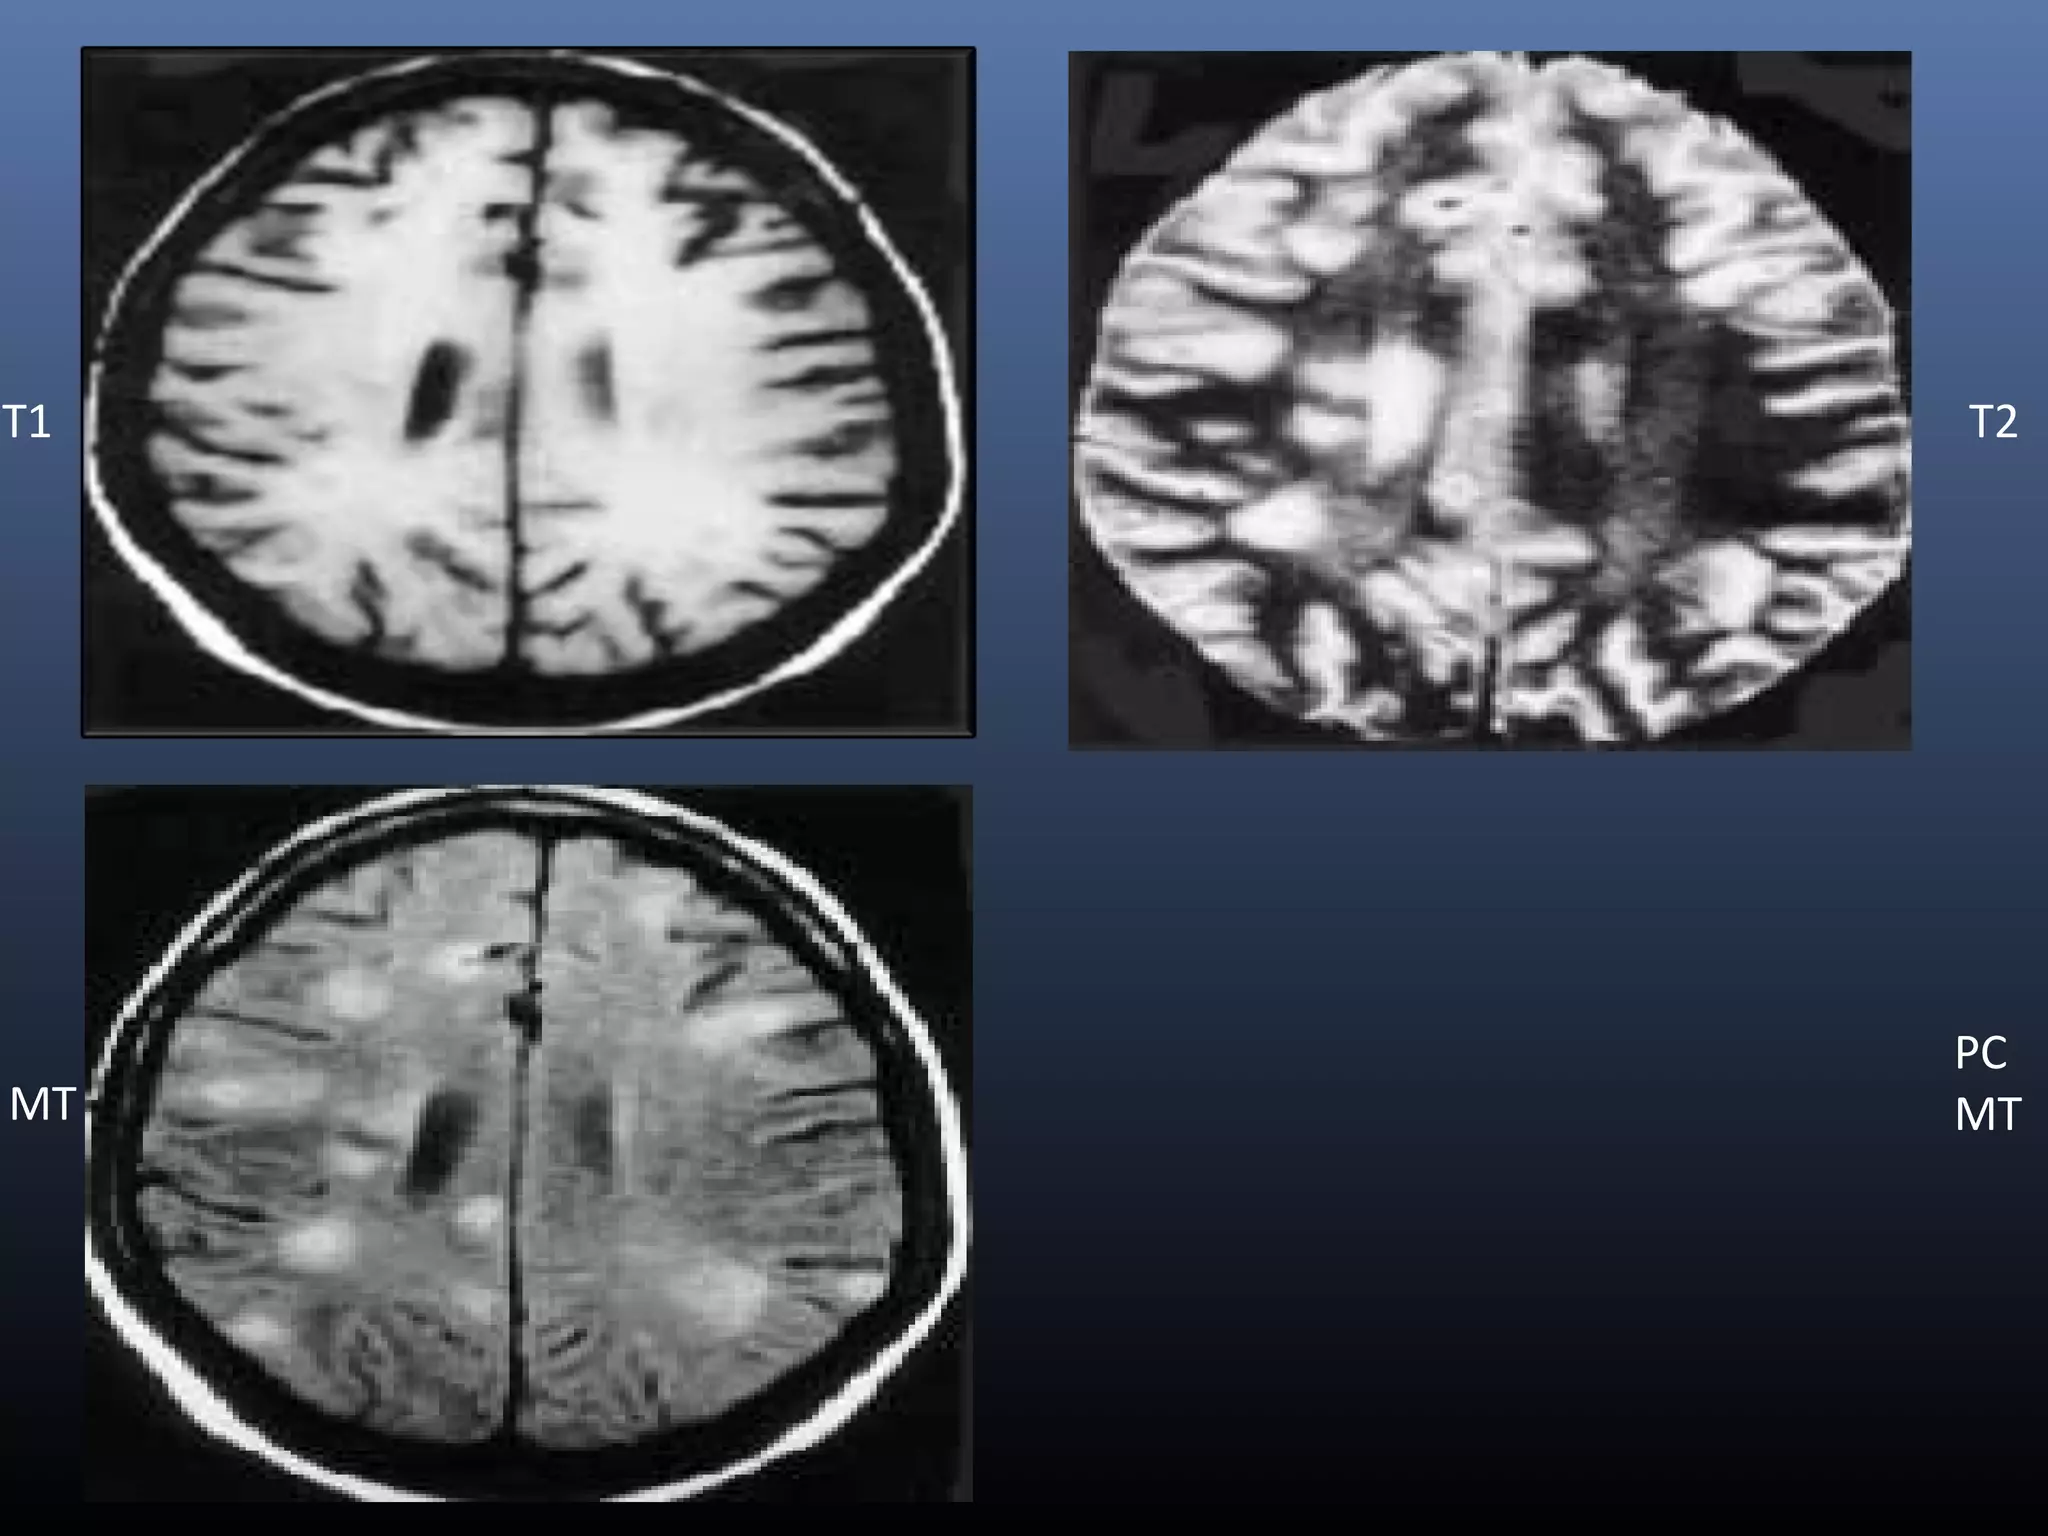

T1 T2

MT

PC

CLINICAL APPLICATION• Useful diagnostictool in characterization of a variety of CNS infection • In detection and diagnosis of meningitis , encephalitis, CNS tuberculosis , neurocysticercosis and brain abscess. TUBERCULOMA • Pre-contrast T1-W MT imaging helps to better assess the disease load in CNS tuberculosis by improving the detectability of the lesions, with more number of tuberculomas detected on pre-contrast MT images compared to routine SE images • It may also be possible to differentiate T2 hypo intense tuberculoma from T2 hypo intense cysticerus granuloma with the use of MTR, as cysticercus granulomas show significantly higher MT ratio compared to tuberculomas

NEUROCYSTICERCOSIS Findings vary withthe stage of disease  T1-W MT images are also important in demonstrating perilesional gliosis in treated neurocysticercus lesions  Gliotic areas show low MTR compared to the gray matter and white matter. So appear as hyperintense BRAIN ABSCESS  Lower MTR from tubercular abscess wall in comparison to wall of pyogenic abscess(~20 vs. ~26)